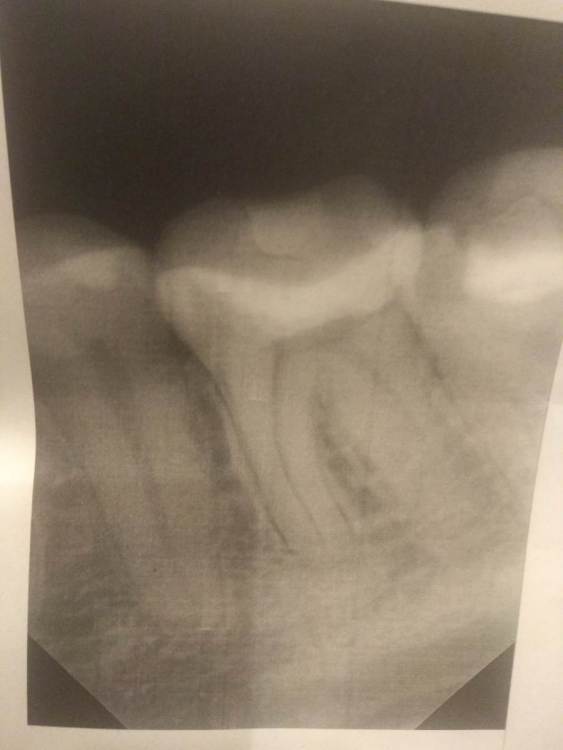

Primavera2023 Опубликовано 2 ноября, 2023 Поделиться Опубликовано 2 ноября, 2023 (изменено) Здравствуйте. Мне 32 года. В конце сентября стал побаливать зуб 3.6. боль была несильная, но регулярная, особенно как реакция на холодное. На зубе уже 7 лет стояла большая пломба. Я пошла к стоматологу, у которого лечилась ранее, и мне обнаружили небольшой кариес сбоку на мезиальной поверхности. Но запись была на 2 месяца вперёд. Я пошла к другому стоматологу. Он поменял старую пломбу, а новый кариес не заметил, как я не говорила. Там была маленькая дырочка на границе десны. От неё шла эта боль. А когда он менял пломбу было совсем почти не больно. До пульпы осталась тоненькая стеночка дентина. Сразу поставил постоянную пломбу, сказал не будет ставить временную. Через несколько дней зуб стал уже ощутимо болеть, боль усиливалась ночью, была пульсирующей. Я пошла к третьему стоматологу, где мне удалили нерв. В процессе пломбировки 3 корневых каналов стоматолог вывел в одном материал за апекс на 3-4 мм вместе с гуттаперчевым штифтом. Канал распломбировали, гуттаперчу достали, а силер АН + нет. После этого стало очень больно накусывать на зуб и боли не проходят уже неделю. Тогда же стоматолог наконец заметил кариес по границе десны. Теперь ещё одну стенку зуба сказал надо убирать. Во вторник будет завершение лечения с установкой титанового штифта. Может не стоит торопиться и подождать ещё неделю, а если боль не пройдёт, проще удалить этот зуб? Денег уже потратила немало, а я получаю МРОТ. Может соседняя 7 встанет со временем на место 6, если ту удалить, а там и дистопированная 8 подтянется? Рентгена после пломбировки каналов сейчас на руках нет. Возьму в следующее посещение. На первом снимке зуб до депульпации после замены пломбы. На втором зуб еще со старой пломбой. (в конце сентября). Изменено 2 ноября, 2023 пользователем Primavera2023 Ссылка на комментарий